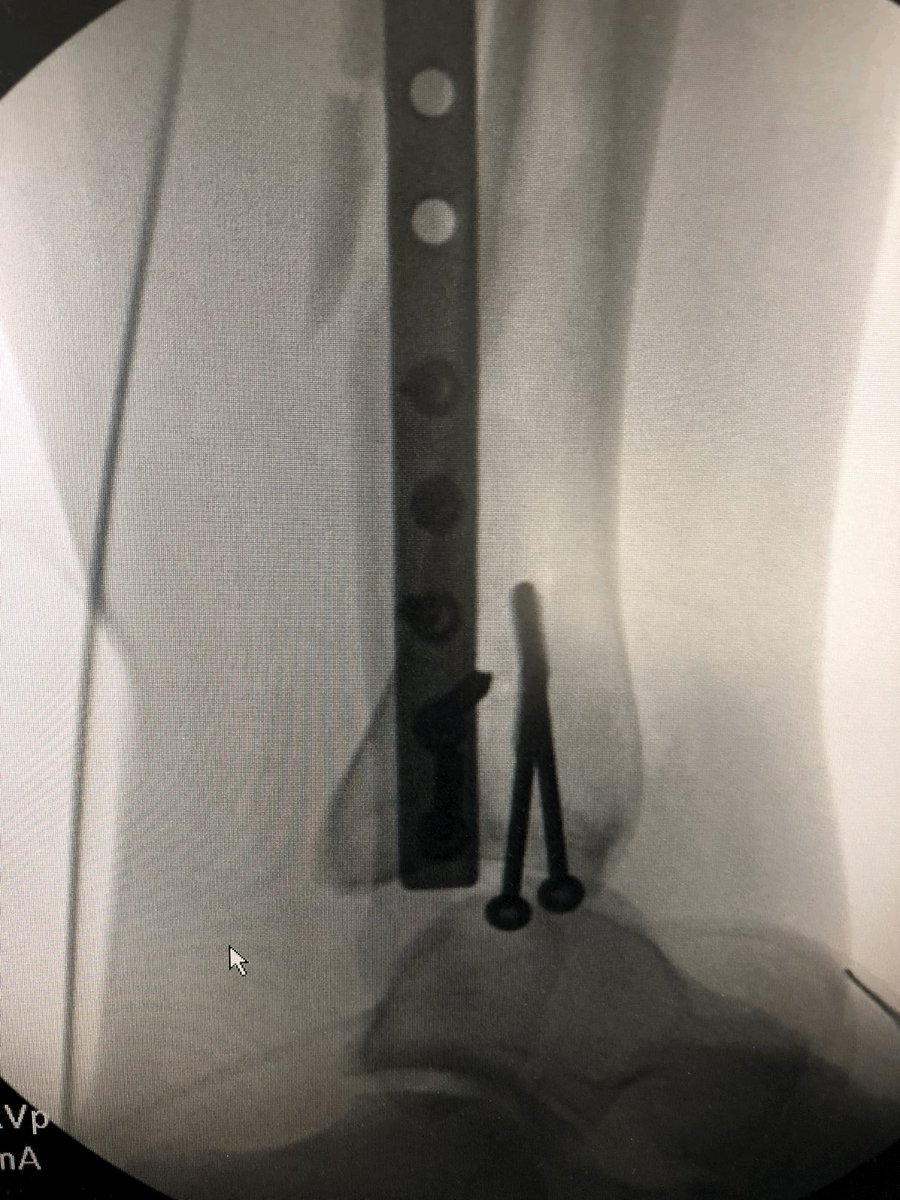

When the syndesmosis is over compressed, the talus is spit forwards. It’s subtle if you’re not looking for it, but once you see it, don’t neglect it. It’s a subluxed incongruent ankle joint. #OrthoX

@DrBhavinJadav

See what’s wrong here?  The large clamp across the ankle is not ‘reducing’ the syndesmosis, it is ‘over compressing’ it. There is a reason we use Position screws across the syndesmosis and not Lag screws. Don’t over compress the syndesmosis, it will push/spit the Talus. #OrthoX